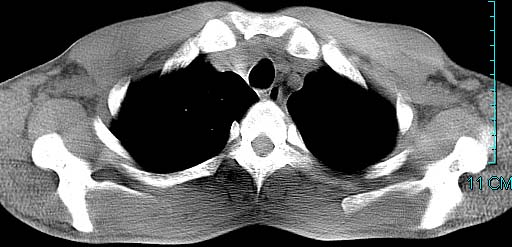

以下是引用ctkz987在2006-3-28 13:04:00的发言:[br]左侧胸腔积液穿刺后多发气液平(多房性),结合临床有高热不除外合并感染。

以下是引用qian在2006-3-28 14:32:00的发言:[br]左肺下叶大片状阴影,密度不均,见有条片影和空洞及气液平,少量胸腔积液伴有胸膜增厚,从图像看积液密度比水的密度高,结合病史,考虑左下肺化脓性炎症伴有脓胸。

以下是引用wawaquan在2006-3-28 22:25:00的发言:[br]左上肺舌段多发斑片影。结合“男24y咳嗽咳痰气促伴高热(38.5--39.5)20多天”及穿刺史,[br]考虑1 左下肺化脓性炎症;2脓胸。

以下是引用乡医在2006-3-28 18:37:00的发言:[br]左侧多发液气平面结合患者男24y咳嗽咳痰气促伴高热(38.5--39.5)20多天,查胸水:ldh239.3,总蛋白59.19,tb-ab阴性,利凡它试验+,红c2.7*109,白c1.08*109,分类淋巴92%分叶8%,考虑1脓胸2肺隔离征感染